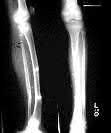

What is the most likely mechanism of failure for the patellar component shown: